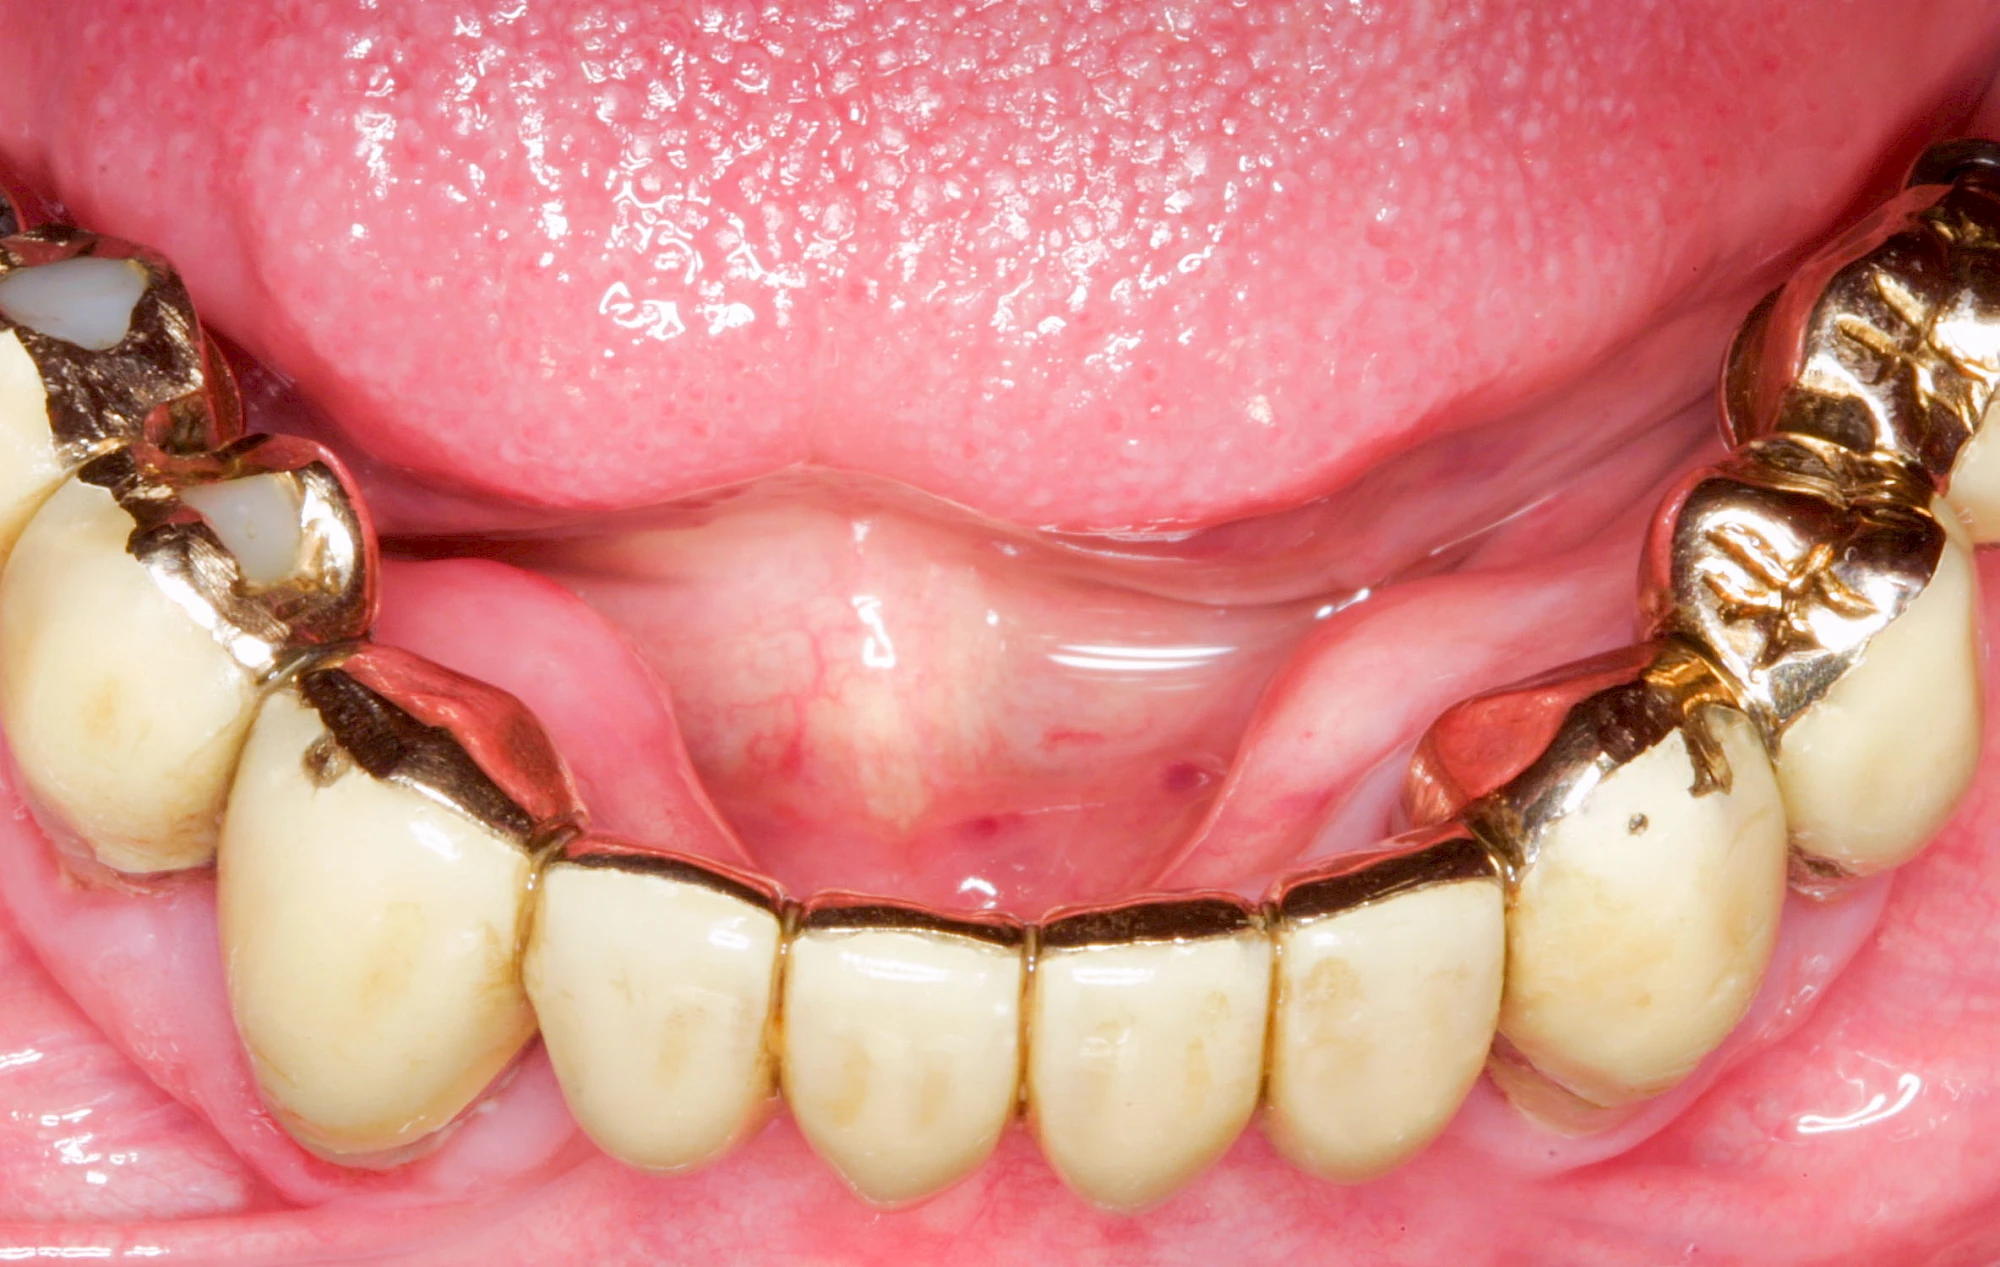

Heute werden in Deutschland Menschen mit Lippen-Kiefer-Gaumenspalten bereits ab Geburt von Experten verschiedener Fachrichtungen (Mund-Kiefer-Gesichtschirurgen, Kieferorthopäden, Logopäden) betreut, damit entsprechende Korrekturen schon frühzeitig erfolgen können. Gerade jedoch bei älteren Menschen ist dies nicht immer geschehen. Diese Menschen tragen häufig technisch aufwendige Zahnprothesen.

Lippen-Kiefer-Gaumenspalten (LKG-Spalte) sind angeborene Fehlbildungen im Mund-Kiefer-Gesichtsbereich. Die Gewebestrukturen im Bereich des Oberkiefers sind im Zuge der Entwicklungen bis zur Geburt nicht zusammengewachsen. Diese Fehlbildung zählt zu den häufigsten Fehlbildungen des Menschen, von 500 Neugeborenen ist eines betroffen. Die Fehlbildungen können sich auf Lippe, Gaumen und Kiefer allein beschränken, treten häufig aber kombiniert und in seltenen Fällen sogar beidseits auf.